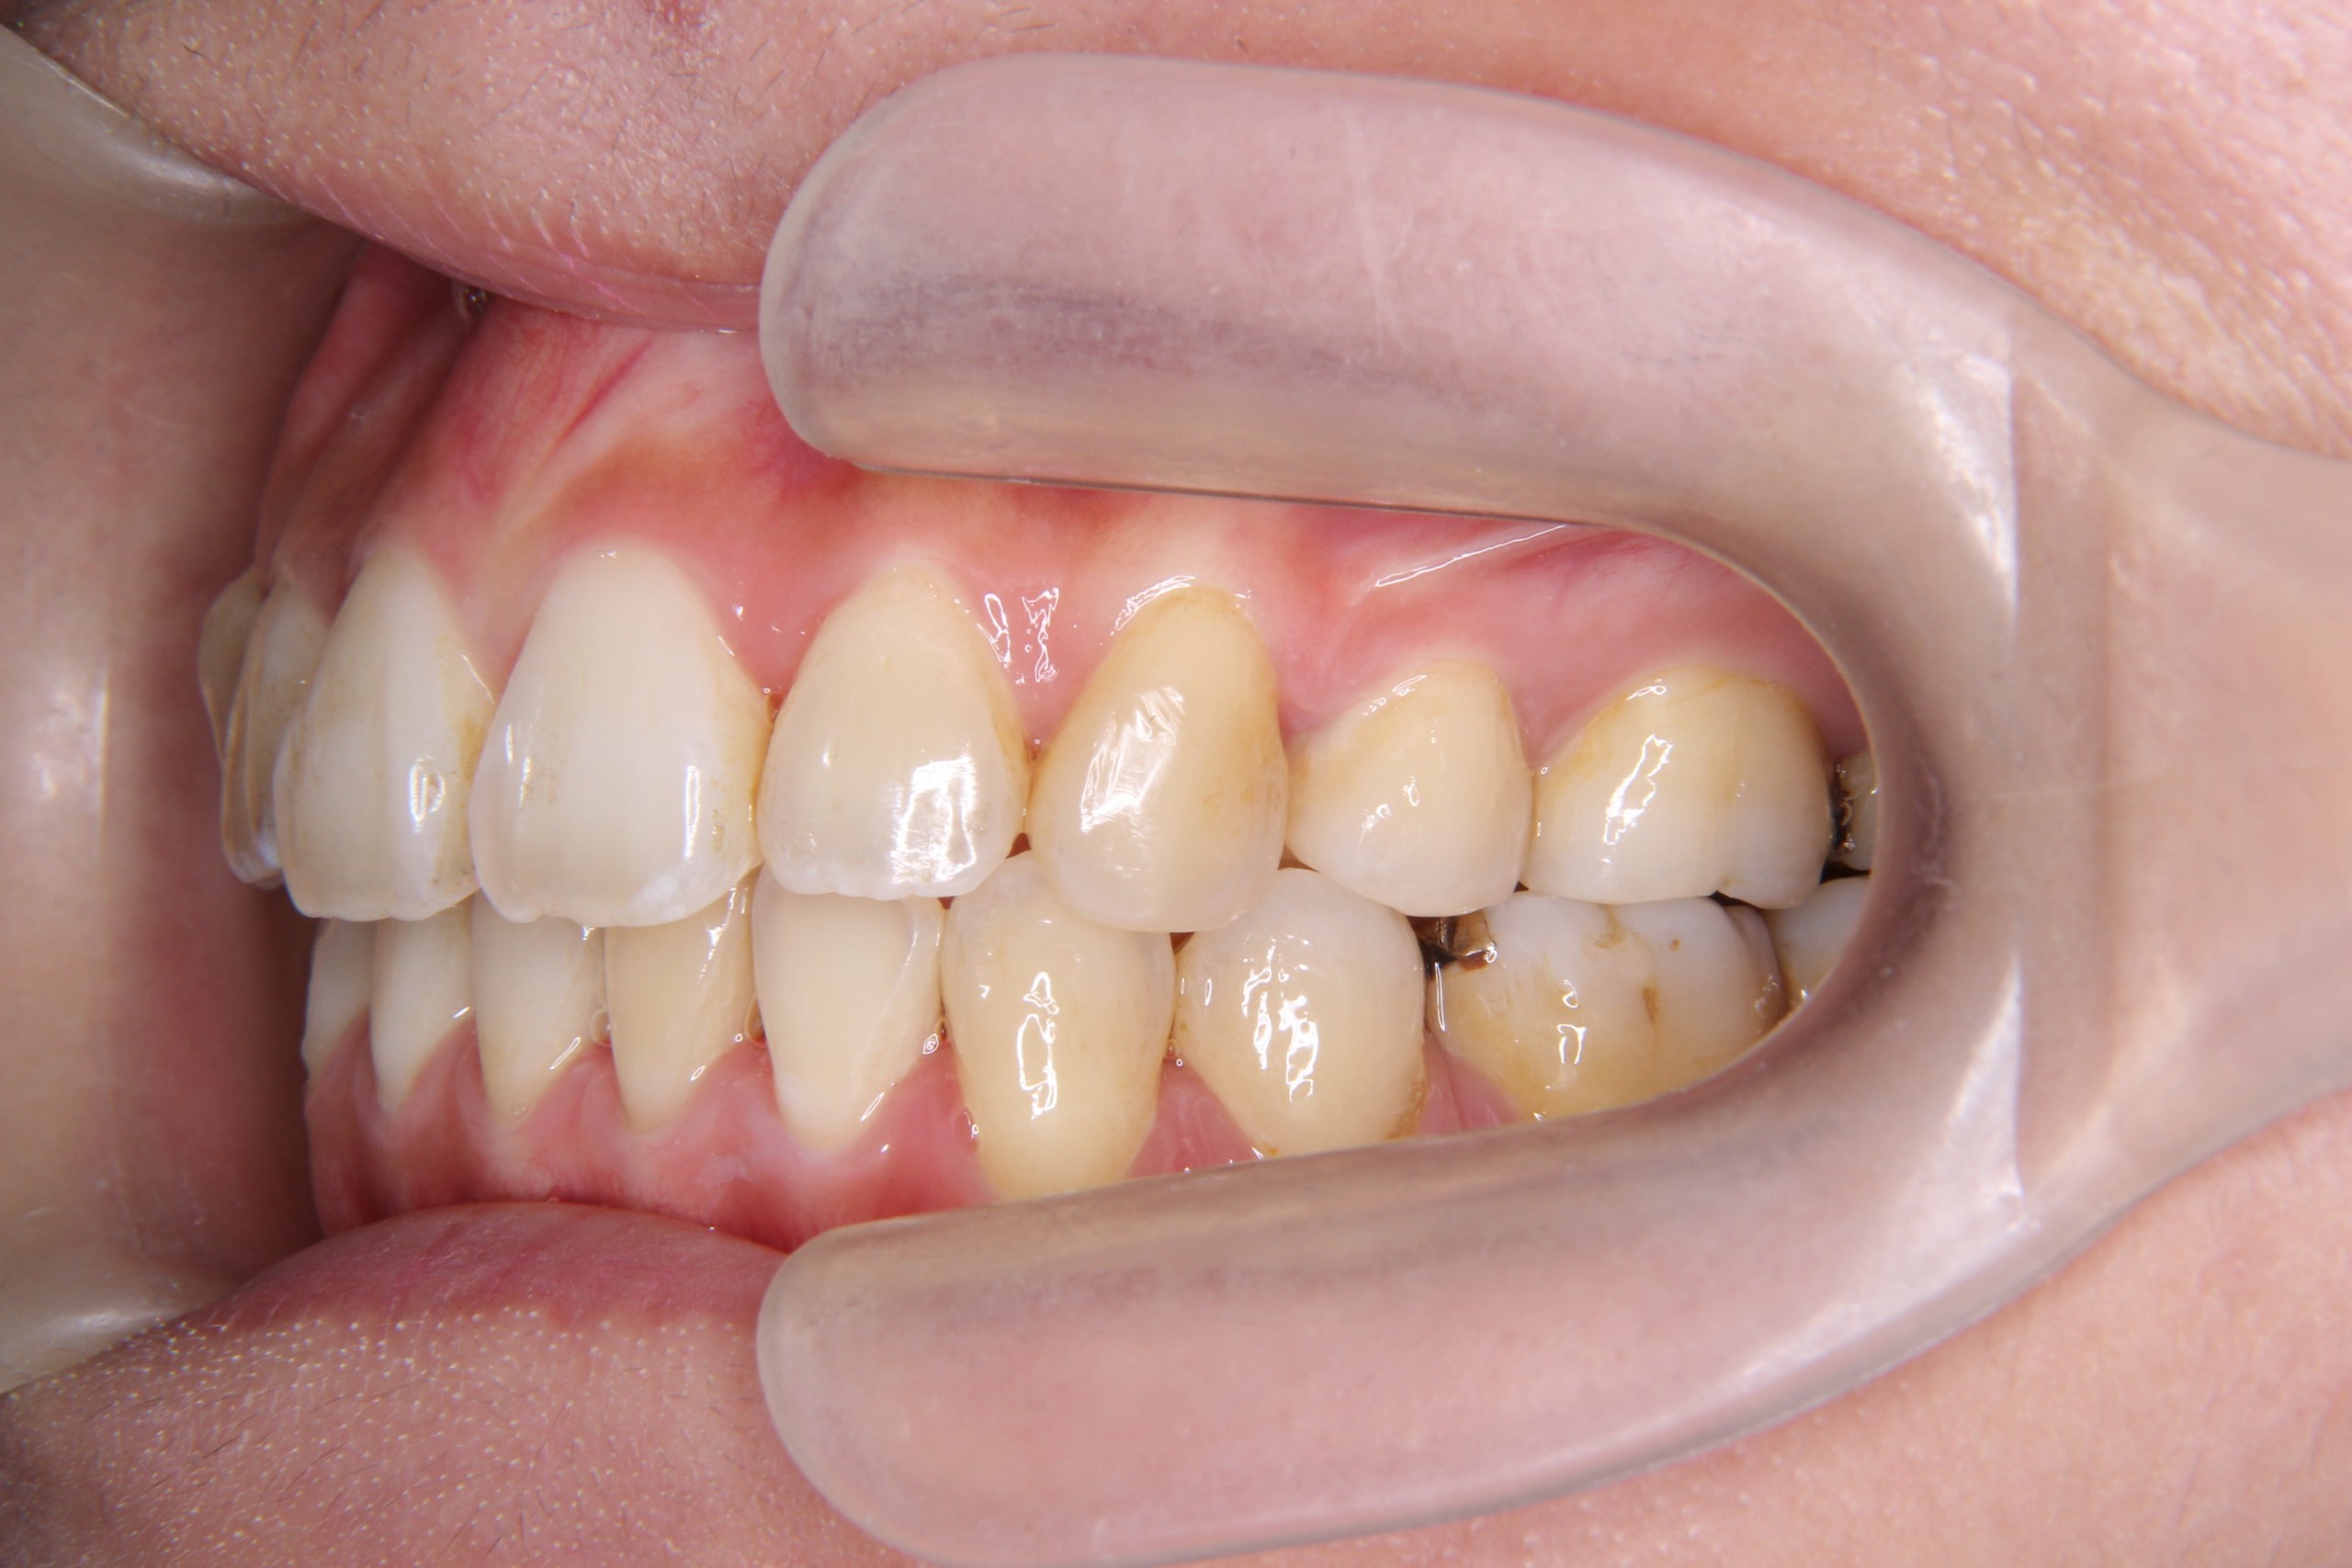

年齢層 20代

性別 男性

主訴 【主訴】出っ歯を治したい 【診断・症状】上下凸凹、出っ歯(上顎前突)

治療費用 検査・診断:38,500-/裏側矯正治療:1,397,000-(※全て税込)

治療期間 約1年半(20回)

抜歯 有(上4,4のみ)

矯正の装置 裏側矯正(舌側矯正)

副作用、リスク 歯肉退縮,歯根吸収,疼痛,咬合の違和感,装置の違和感,虫歯,歯肉炎

case15_出っ歯_before

Before

case15_出っ歯_after

After